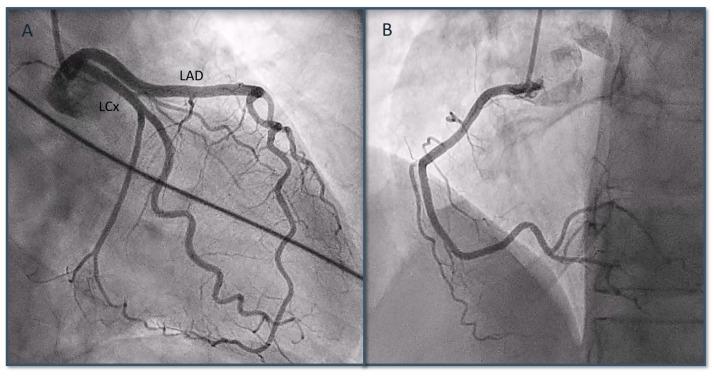

曲妥珠单抗和帕妥珠单抗治疗HER2阳性转移性乳腺癌期间的应激性心肌病综合征

Takotsubo Syndrome during Pertuzumab and Trastuzumab Therapy for HER2-Positive Metastatic Breast Cancer.

Pertuzumab and trastuzumab have been shown to improve the outcomes of patients with metastatic breast cancer, with a rate of left ventricular dysfunction of approximately 6%. We report the case of a postmenopausal woman who presented with Takotsubo syndrome during maintenance therapy with pertuzumab and trastuzumab, in association with fulvestrant (an anti-estrogen) and denosumab. After normalization of cardiac function, therapy with pertuzumab and trastuzumab was resumed in the absence of new cardiac toxicity. We report the first clinical case of Takotsubo syndrome during double anti-HER2 blockade in association with an antiestrogen. Furthermore, we show how anti-HER2 therapy can be safely resumed after the detection of Takotsubo syndrome.

摘要

帕妥珠单抗和曲妥珠单抗已被证明可改善转移性乳腺癌患者的预后,左心室功能障碍发生率约为6%。我们报告了一例绝经后女性病例,该患者在接受帕妥珠单抗、曲妥珠单抗联合氟维司群(一种抗雌激素药物)和地诺单抗维持治疗期间出现了Takotsubo综合征。在心脏功能恢复正常后,在没有新的心脏毒性的情况下恢复了帕妥珠单抗和曲妥珠单抗治疗。我们报告了首例在双重抗HER2阻断联合抗雌激素治疗期间发生Takotsubo综合征的临床病例。此外,我们展示了在检测到Takotsubo综合征后如何安全地恢复抗HER2治疗。